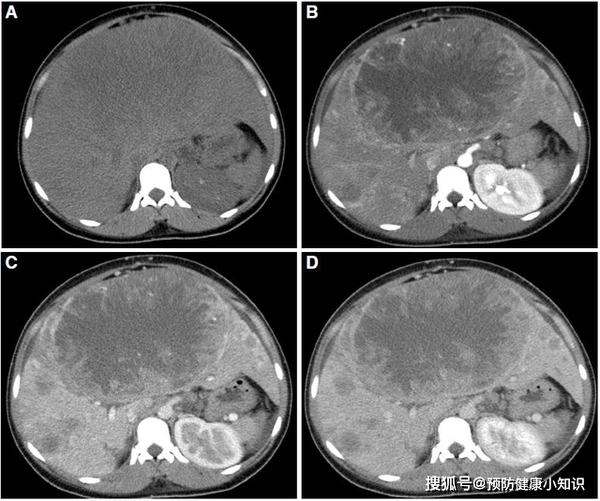

影像學檢查包括增强CT、超聲和磁共振,對於難以確診的病例,肝血管造影可能有助於診斷。如果影像學有特徵性的表現,且抱伴有甲胎蛋白升高,診斷可以明確。必要的時候,可以在超聲或CT引導下做肝活檢,以進一步明確診斷。